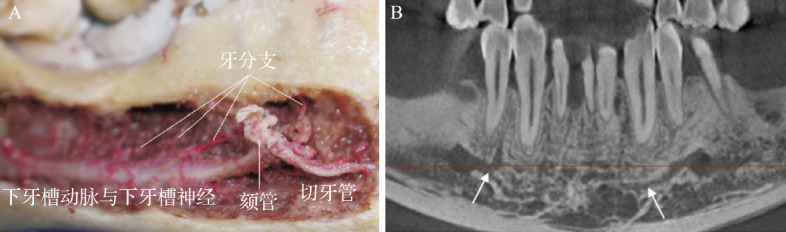

在下颌前区进行种植手术时,可能会损伤下颌切迹管、舌孔、口底血管等重要解剖结构,从而导致口底血肿、窒息、疼痛、麻痹等症状。严重者可危及生命。下颌前牙区牙槽骨空间不足,血管和神经的解剖变异增加了种植手术中血管和神经损伤的风险。一旦发生血管损伤,应进行气道控制和止血;一旦发生神经损伤,应拔除种植体并及早就医。为了避免下颌前牙区种植手术中的血管和神经损伤,必须熟悉解剖结构,术前做好锥形束计算机断层扫描和设计,术中利用数字化技术实现种植体的准确植入。本文总结了下颌前牙区的解剖结构,探讨了下颌前牙区血管、神经损伤的预防策略,并对发生血管、神经损伤后的治疗方法进行了探讨,以期为临床提供参考。

Important anatomical structures such as mandibular incisive canal, tongue foramen, and mouth floor vessels may be damaged during implant surgery in the mandibular anterior region, which may lead to mouth floor hematoma, asphyxia, pain, paresthesia and other symptoms. In severe cases, this can be life-threatening. The insufficient alveolar bone space and the anatomical variation of blood vessels and nerves in the mandibular anterior region increase the risk of blood vessel and nerve injury during implant surgery. In case of vascular injury, airway control and hemostasis should be performed, and in case of nerve injury, implant removal and early medical treatment should be performed. To avoid vascular and nerve injury during implant surgery in the mandibular anterior region, it is necessary to be familiar with the anatomical structure, take cone-beam computed tomography, design properly before surgery, and use digital technology during surgery to achieve accurate implant placement. This article summarizes the anatomical structure of the mandibular anterior region, discusses the prevention strategies of vascular and nerve injuries in this region, and discusses the treatment methods after the occurrence of vascular and nerve injuries, to provide clinical reference.